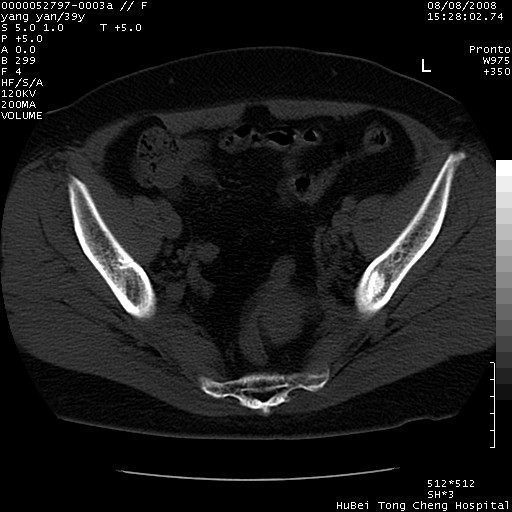

患者 女,39岁。因外伤检查,偶然发现。

典型!双侧骶髂关节致密性骨炎。

典型!病变主要累及双侧髂骨。常见于育龄期妇女。

致密性骨炎,一般不跨越关节面,可是这个骶骨关节面也有硬化。

髂骨致密性骨炎系一种以骨质硬化为特点的非特异性炎症,有高度致密的骨硬化现象,尤其以髂骨下2/3更为明显,但关节间隙则无改变。因位于骶髂关节,且该关节症状明显,故又称之为“骶髂关节致密性骨炎”。 本病90%以上为中年女性,以妊娠后期、尤其分娩后为多见,亦可见于尿路或女性附件慢性感染后,或盆腔内其他感染。此外,臀骶部的外伤亦可诱发或引起本病。  妊娠、分娩及外伤均可引起骶髂关节韧带的撕裂而易使局部的血供受阻。因此早期局部呈现充血、水肿及渗出增加等,渐而局部出现增生与变性反应,随着胶原纤维的致密化而向硬化演变;血管形成厚壁血管,易闭塞而引起髂骨耳状面处缺血和缺氧,骨质呈现硬化性改变,以致手术时局部出血较少。骶髂关节囊壁显示纤维增生、弹性降低及松动样改变。继发于盆腔内炎症者亦出现相类似的病理改变,可能系细菌内毒素作用所致。